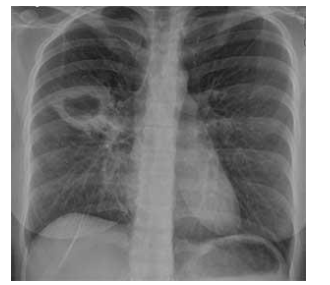

Adolescente de 12 anos, sem comorbidades, apresentou contato domiciliar de tuberculose pulmonar e vem para investigar infecção latente por M. tuberculosis. No momento, está assintomática. Realizou PPD com resultado de 10mm e radiografia de tórax demonstrada abaixo.

Enunciado 4059112-1

Diante do caso, qual a conduta mais aceitável?